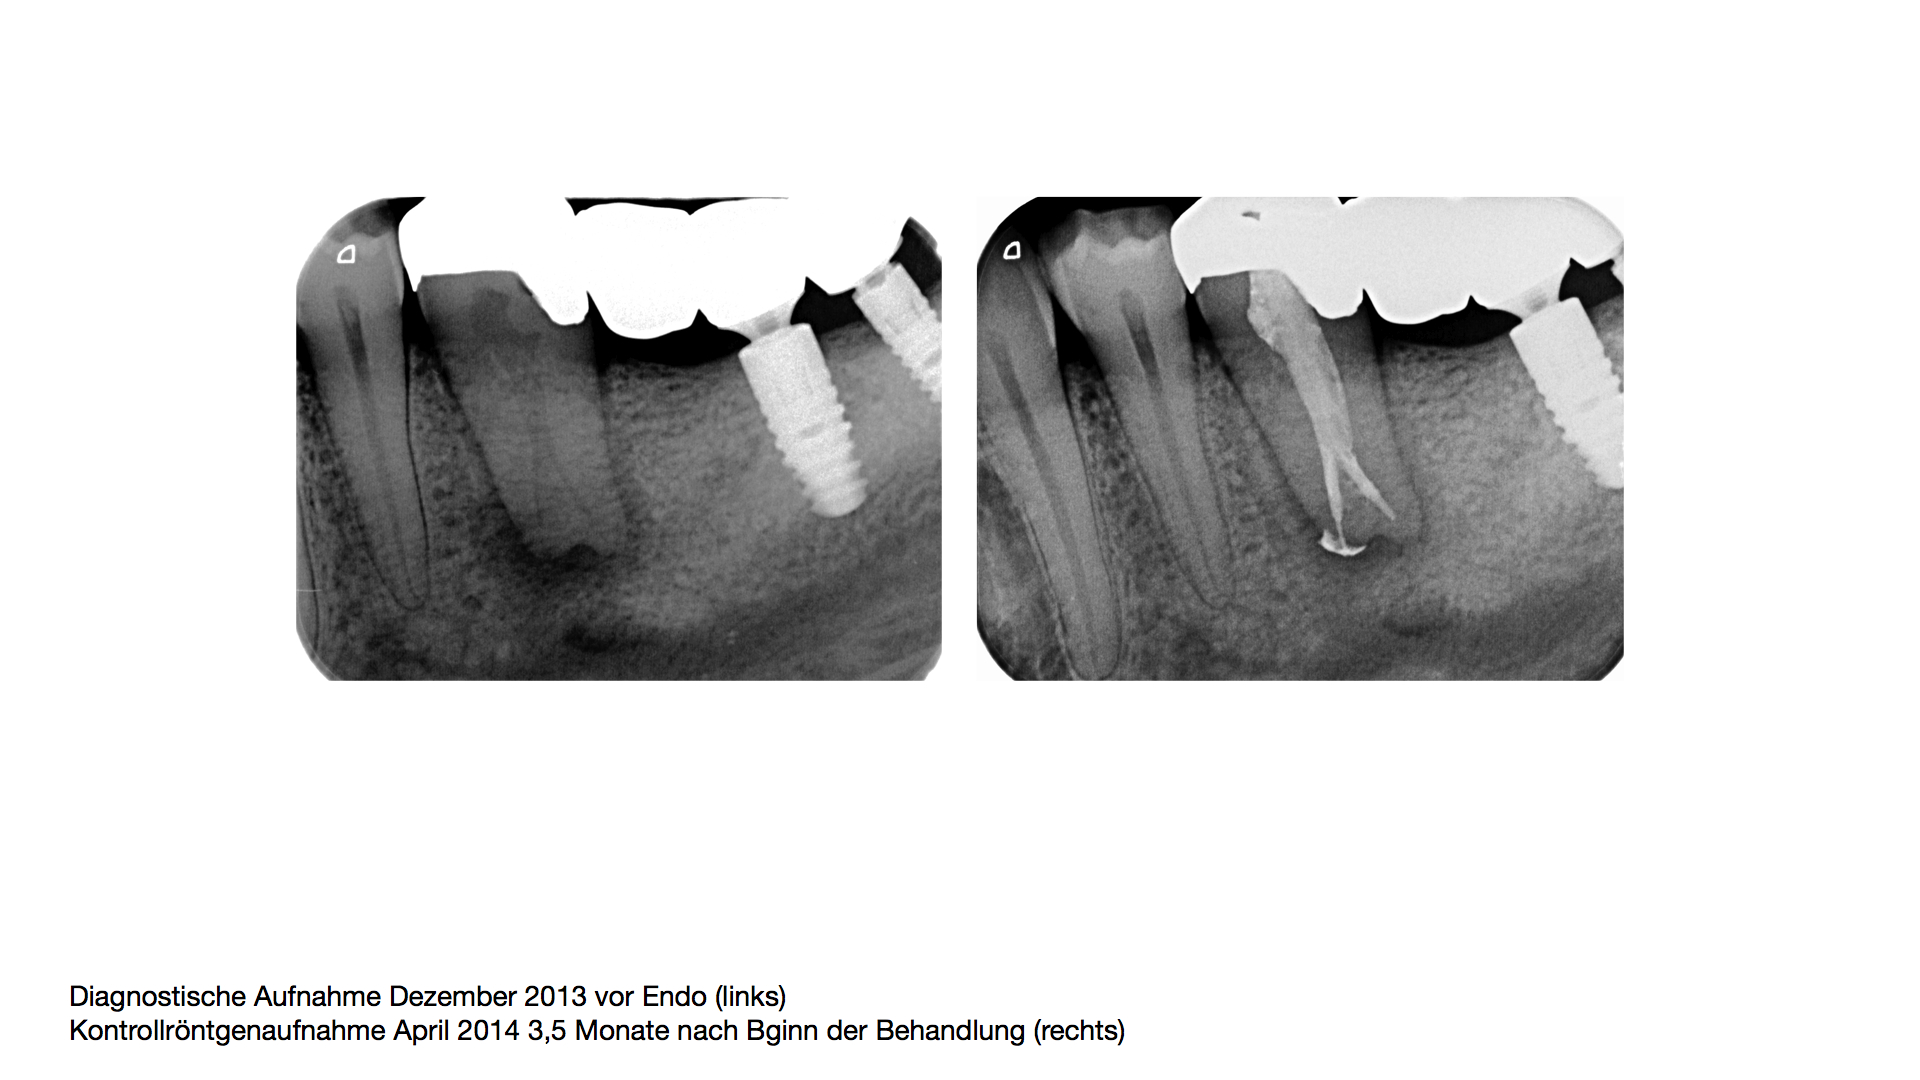

Rickes_1a.006 Veröffentlicht 7. April 2014 am 1920 × 1080 in Neue Wege gehen – UK – Prämolar, 90 Grad gedreht – so ging´s weiter